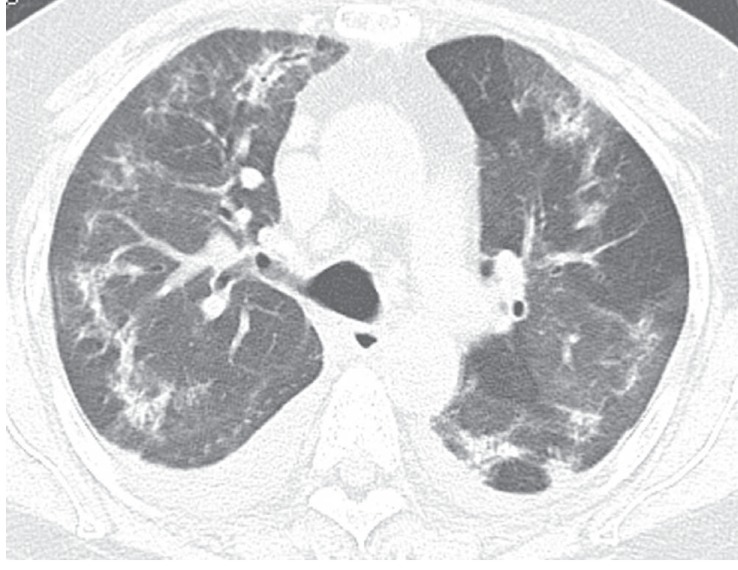

Figure 3

A 65-year-old male with amiodarone pulmonary toxicity (APT) exhibiting a mixed organizing pneumonia and interstitial fibrosis pattern. (A) A computed tomography (CT) scan obtained without intravenous contrast injection revealed consolidation in the posterior segment of the right upper lobe, which exhibited high CT-attenuation compared with the muscles of the thorax. (B) A CT scan at the level of both lower lobes showed interlobular septal thickenings in both lower lobes (arrowheads) and small subpleural consolidations in the left lower lobe (arrows). (C) In the upper abdomen, the liver showed a diffuse high attenuation, which is a characteristic CT finding of APT caused by iodine accumulation in the liver.

There are two major hypotheses regarding APT: immune-mediated hypersensitivity and the direct cytotoxicity of drug-induced phospholipidosis [6,13]. Moreover, amiodarone has several pharmacological properties that contribute to its toxicities [2,14], including the presence of two iodine atoms that result in the release of 7 mg iodine per 200 mg amiodarone (normal iodine intake, 150 to 200 µg/day), its lipophilic nature and high affinity for tissue accumulation, long half-life, and a large distribution volume. Consequently, amiodarone accumulates in fatty tissue, the liver, and lungs in chronic users, which leads to drug-induced direct organ toxicities. Iodine is highly attenuated on CT; therefore, the high attenuation of these organs on nonenhanced CT might represent iodine accumulation in the lungs and/or liver of chronic amiodarone users [6]. Increased lung attenuation seems to present in more advanced APT cases [7]. Case six in the current study showed characteristic high attenuation on nonenhanced CT in both the liver and lungs, which suggested iodine accumulation related to chronic amiodarone use (Fig. 3A and 3C).